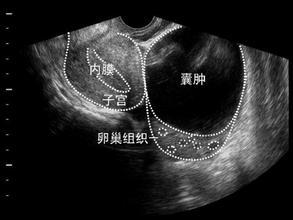

卵巢囊肿